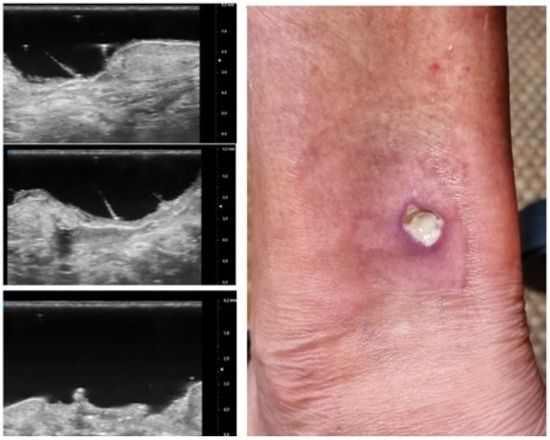

Moreover, the presence of similar UHFUS findings between the pustular and ulcerative phenotypes in T0, suggested the idea, not yet confirmed in the literature, that the pustular phenotype was an early stage of the ulcerative one, in agreement with the assumption of Powell et al. this hypothesis could be supported by our population’s anamnestic data that reveal a clinical onset with confluent or non-confluent pustules in 5 patients. (Figure 7) [12].

Figure 5. Patient affected by ulcerative Pyoderma Gangrenosum (PG) of the calf during the non-inflammatory phase: clinical aspect of the wound and its Ultra-High Frequency UltraSound (UHFUS) correlates.